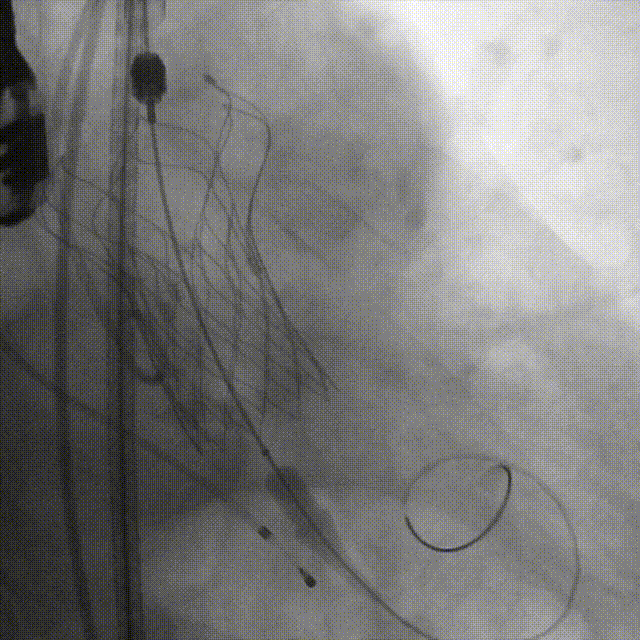

主动脉根部造影

导丝跨瓣

瓣膜定位,0位释放

释放2/3处造影确认植入深度

释放瓣膜

最终形态造影